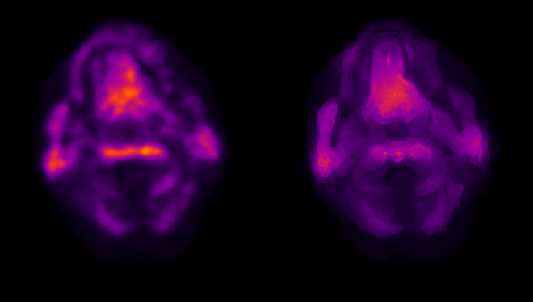

Figure: Coregistered conventional PET and MICSI-PET amyloid images across a range of amyloid burdens, highlighting differences in apparent cortical sparing: left, amyloid-negative with strong gray/white contrast; right, amyloid-positive with reduced gray/white contrast.